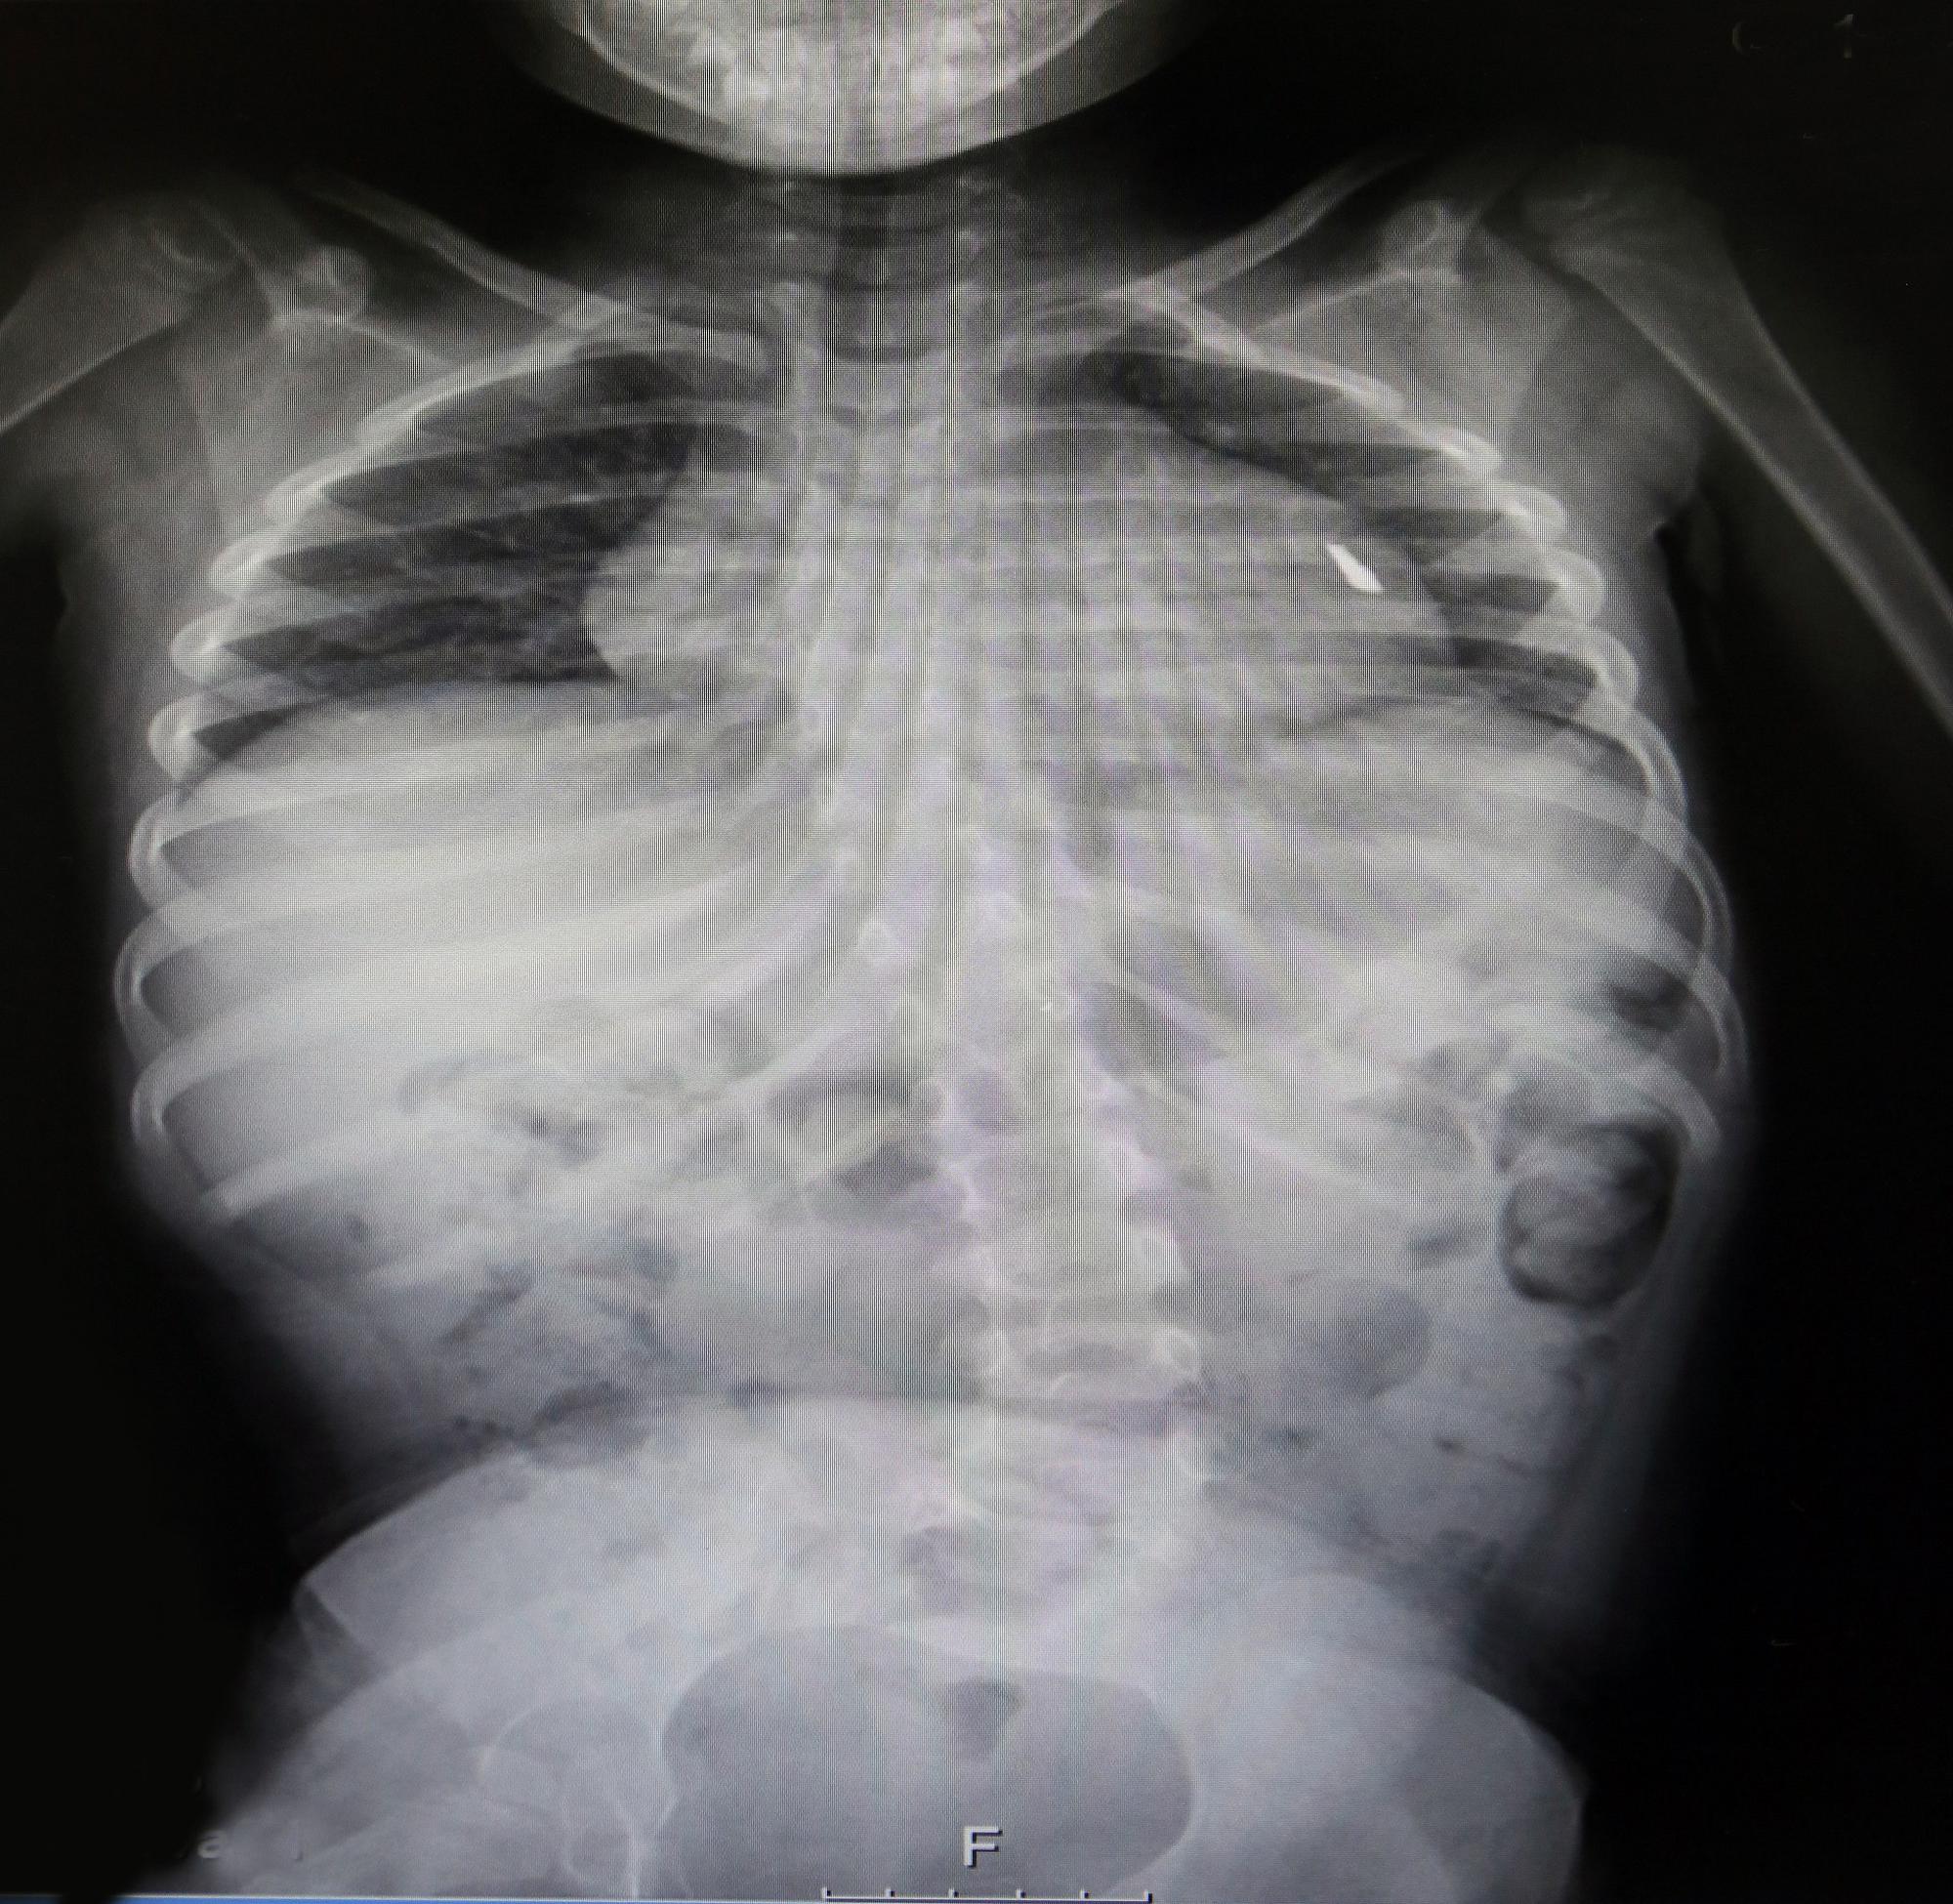

עם הגעתה לרמב"ם, בצעו הרופאים מספר בדיקות דימות, על מנת לבדוק מה מיקומו המדויק של הרסיס ומה גודל הסכנה. תוצאות הבדיקה הותירו את הרופאים המומים: הרסיס חדר למעשה את קרומי הלב ואף עבר באופן חלקי את דופן הלב עצמו. במשך חודשים ארוכים הילדה הקטנה הסתובבה עם רסיס נעוץ בליבה, כאשר כל דקה יכולה להיות האחרונה בחייה.

בצילום הרנטגן: הרסיס בליבה של הפעוטה, כפי שנראה בבדיקה.